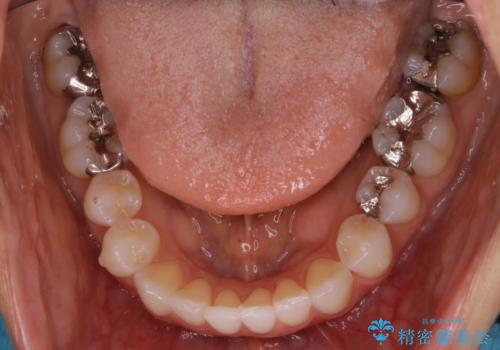

- 前歯のガタつき改善を主訴にご来院されました。

ガタつき自体は軽度で、奥歯の噛み合わせのズレもほとんどなかったため、非抜歯でマウスピース矯正装置を選択しました。

歯列の幅の拡大と歯を小さくする調整を行うことで並べるスペースの確保を行いました。この方法は、ガタつきをとりたいところに直接スペースを作ることができるので治療期間を短縮することができ効率的です。

ディスキング(IPR)

歯のガタつきをとるためのスペース作りの方法の一つにディスキング(IPR)という方法があります。

歯と歯の間を一ケ所あたり最大0.5mmまでの範囲内で削ることで歯自体が少し小さくなり、それにより作られるスペースを数ヶ所分合わせることで合計で数mmの大きなスペースが作れるという方法です。

当院ではなるべく歯の機能や見た目に影響の出ないよう、作業時に拡大鏡の使用や削るタイミングの微調整を行っています。